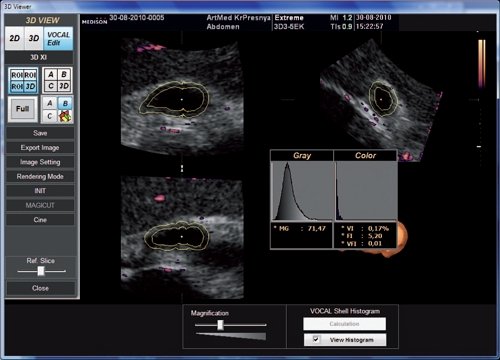

Суть манипуляций с трехмерными данными в VOCAL заключается в том, что зону интереса (орган или патологический очаг любой формы) позиционируют на мониторе в одной из контрольных плоскостей (A, B или C) таким образом, чтобы ось вращения проходила через ее центр (рис. 1). Затем в меню задается шаг вращения объекта в 12, 18 или 30° и способ, которым будет выполняться оконтуривание (сегментация) изображения: ручной или автоматический (рис. 2). После завершения оконтуривания программа автоматически рассчитывает объем зоны интереса (рис. 3). С помощью функции Shell Histogramm можно рассчитать медиану эхогенности зоны интереса, а также, если трехмерное сканирование было выполнено в режиме энергетического допплера (ЭД), индексы васкуляризации, потока и перфузии (рис. 4). Индекс васкуляризации (VI) является отношением числа цветных вокселей к общему числу вокселей, из которых состоит трехмерная эхограмма, т.е. он отражает "насыщенность" объекта сосудами. Индекс потока (FI) представляет собой медиану яркости цветных вокселей: чем выше скорость кровотока, тем ярче энергетические допплеровские сигналы и тем соответственно больше значения индекса потока. Индекс перфузии (VFI) является соотношением средневзвешенного числа цветных вокселей к общему числу вокселей в трехмерной эхограмме. Все эти расчеты можно проводить многократно в режиме off-line, т.е. работая с "виртуальным пациентом".

Рис. 4. Вычисление средней эхогенности (MG) и допплеровских индексов (VI, FI, VFI) для стенки желчного пузыря.